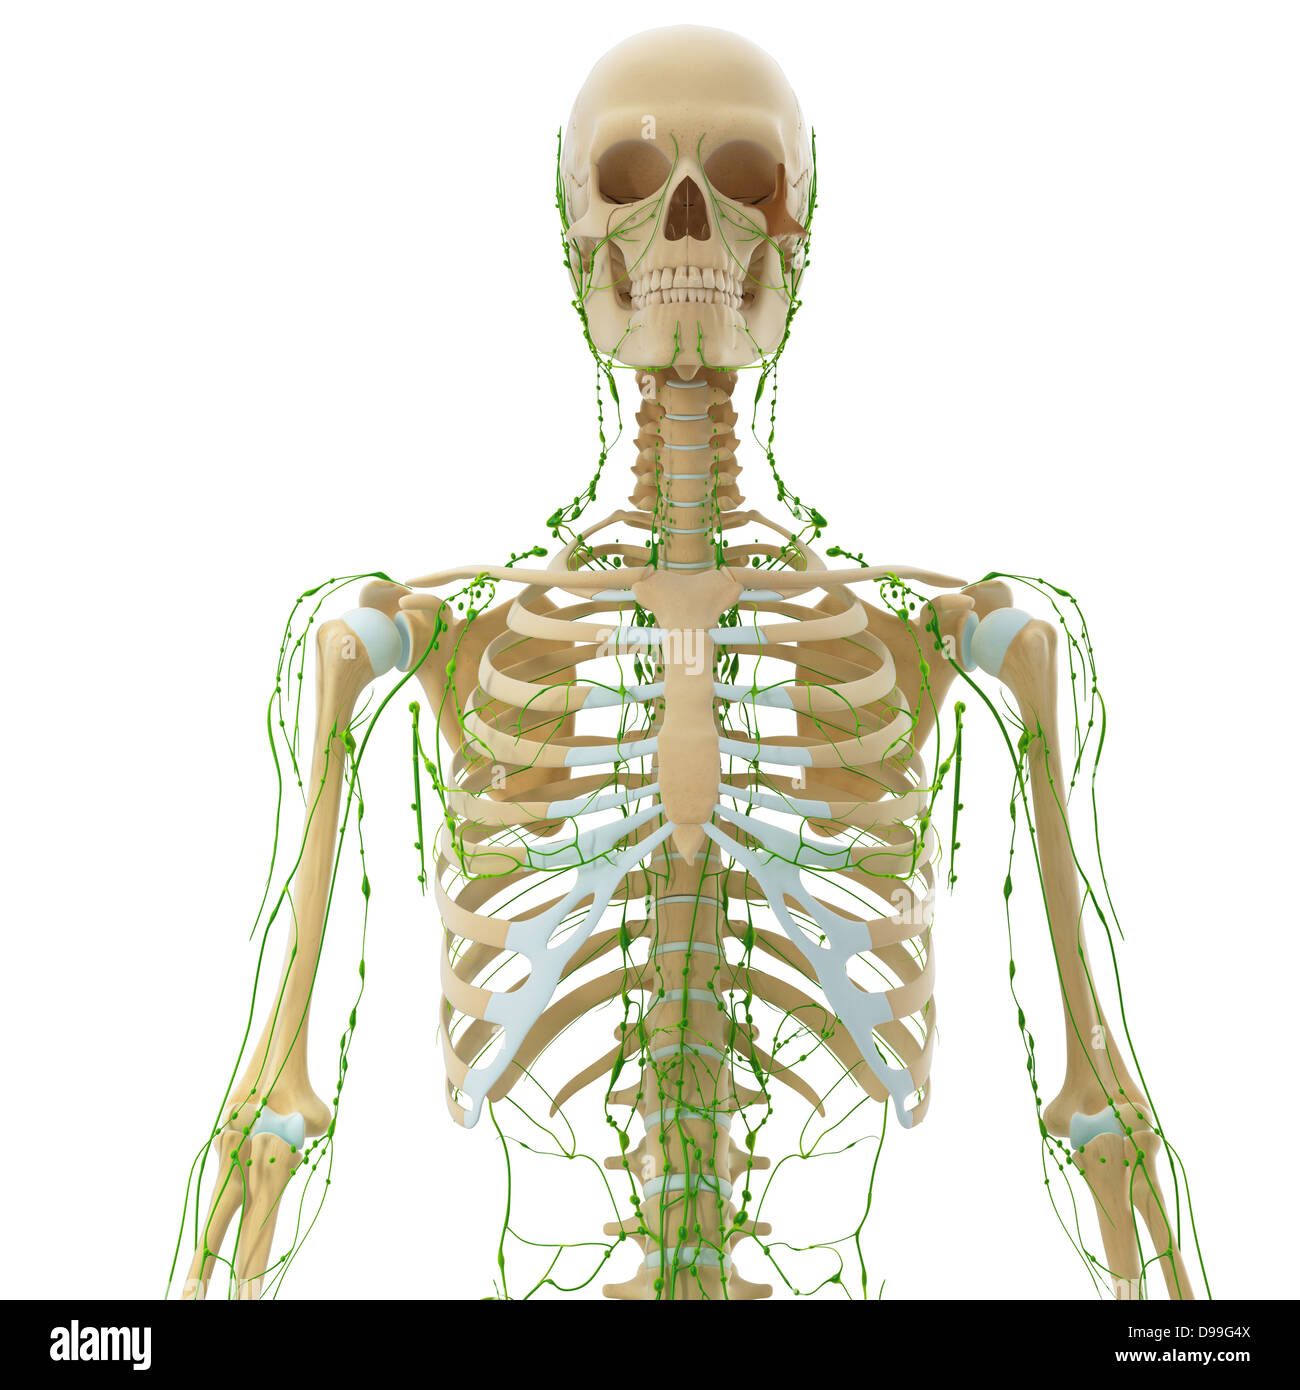

Männchen anatomie Stockfotos & Bilder

Suchergebnisse für Männchen anatomie Stock-Fotos & Bilder (86,080)